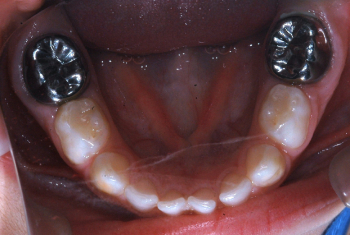

Después: